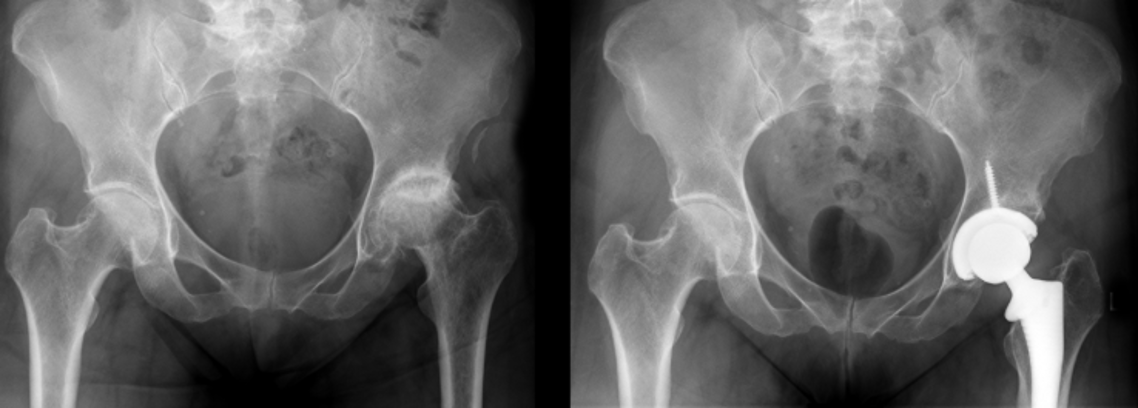

Joint Replacement Surgery (Hip & Knee)

Replacing damaged joints to restore function and alleviate pain.

What is Joint Replacement Surgery?

Replacement of a damaged joint with an artificial one made of metal, ceramic, or plastic.

How is Joint Replacement Surgery Performed?

The damaged joint is removed and replaced with a prosthesis fixed securely to allow smooth movement.